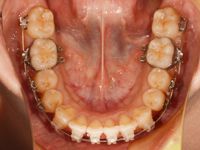

それでは、まずは調整前のお口の中の様子です。

今回はレントゲンを撮って、歯の根っこの並びを確認し、下の前歯のマルチブラケット装置の付け直しをしました![]()

下の前歯4本には今まで透明のレジンでできた仮の装置が付いていたのですが、全部セラミックの装置に付け替えました![]()

これで、歯についているすべての装置が、本来のセルフライゲーションブラケット装置(クリッピーC)になりました![]()

調整後のお口の中です。

マルチブラケット装置の付ける位置を変えると、今まで着けていた太いワイヤーが入れられなくなったので、ワイヤーのサイズを下げて、少し柔らかいワイヤーに変えました